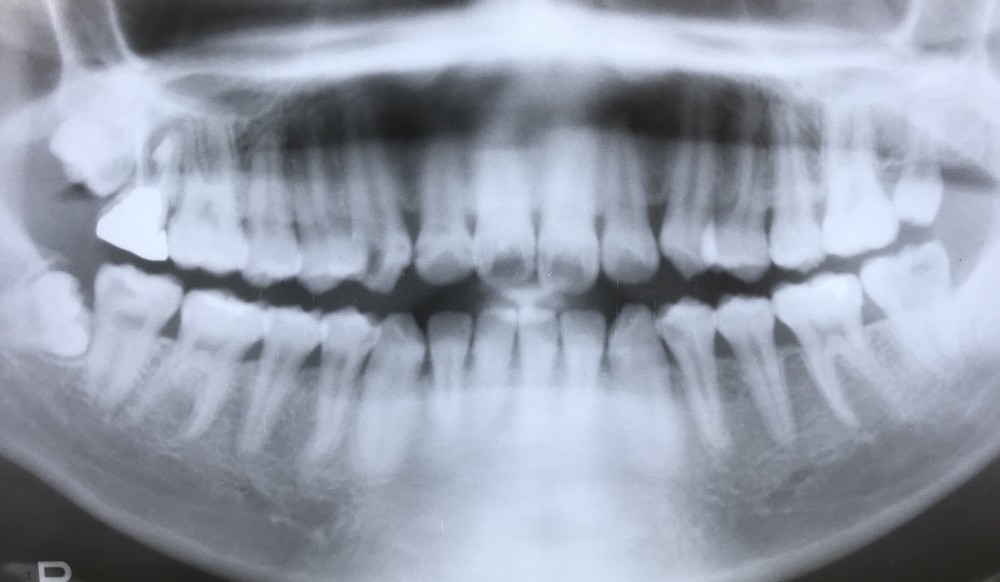

下の写真は、3年後のものです。

左上8が、抜歯した左上7のスペースに萌出したことが確認出来ます。